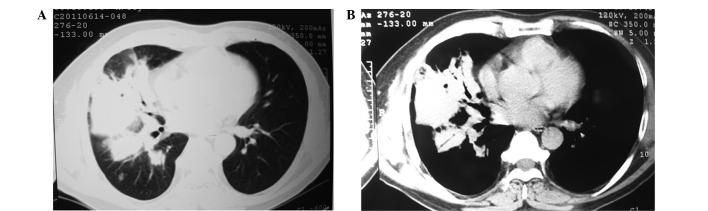

In the present study, the case of a 54-year-old male patient diagnosed with pulmonary histoplasmosis is reported, with the aim to increase the understanding of the disease characteristics and thereby facilitate the diagnosis and treatment of pulmonary histoplasmosis. Clinical manifestations, diagnosis, treatment and clinical outcomes of the present case of pulmonary histoplasmosis were described. In addition, 76 histoplasmosis patients with complete clinical data were reviewed by searching the literature for relevant studies published during 1990 and 2015. The disease was mainly manifested as cough in the present case, while imaging examination detected a lump shadow in the right lung, accompanied by exudative lesions. Initially, the patient was suspected to have bacterial pneumonia, but subsequently the diagnosis of pulmonary histoplasmosis was confirmed by lung biopsy. The symptoms were alleviated following itraconazole treatment. The patient was physically stable and had no recurrence during the subsequent follow-up period. In conclusion, pulmonary histoplasmosis is characterized by non-specific clinical and imaging manifestations, and lung tissue biopsy or respiratory pathogen culture are regarded as the diagnostic gold standards. Individualized antifungal medication should be administered based upon the patients' situation in terms of dosage and duration.

本研究报告了一例54岁男性肺组织胞浆菌病患者的病例,旨在提高对该病特征的认识,从而促进肺组织胞浆菌病的诊断和治疗。描述了本例肺组织胞浆菌病的临床表现、诊断、治疗及临床结局。此外,通过检索1990年至2015年期间发表的相关研究文献,对76例有完整临床资料的组织胞浆菌病患者进行了回顾。本病例中疾病主要表现为咳嗽,影像学检查发现右肺有肿块阴影,并伴有渗出性病变。最初,患者被怀疑患有细菌性肺炎,但随后经肺活检确诊为肺组织胞浆菌病。伊曲康唑治疗后症状缓解。患者身体状况稳定,在随后的随访期间无复发。总之,肺组织胞浆菌病具有非特异性的临床和影像学表现,肺组织活检或呼吸道病原体培养被视为诊断的金标准。应根据患者情况在剂量和疗程方面给予个体化抗真菌药物治疗。